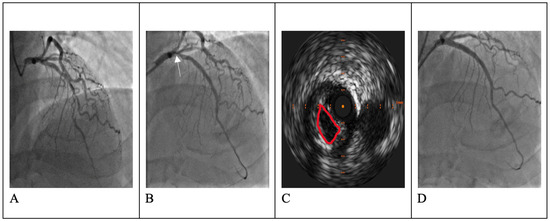

The Middle Meningeal Artery (MMA) occupies a pivotal role in the pathophysiology of migraine, functioning as a vascular and neuroimmune interface that precipitates the characteristic pulsatile pain. The inhibition of this pathophysiological cascade has been investigated as a therapeutic strategy. However, fewer than a dozen centers globally have disseminated procedural or mechanistic data. Given the nascency of this field and the imperative for standardization, the present review synthesizes mechanistic and clinical evidence underpinning intra-arterial pharmacological modulation of the MMA for migraine management. Methods: A focused narrative review was undertaken, drawing upon select but influential studies from pioneering research groups investigating intra-arterial interventions targeting the MMA. The extant literature was thematically categorized and organized according to the loci of cascade interruption and their corresponding clinical outcomes. Results: Since 2009, intra-arterial therapies for severe headache syndromes have evolved, initially utilizing nimodipine for vasospasm-related headaches, progressing to verapamil for reversible cerebral vasoconstriction, and more recently, lidocaine for refractory or status migrainosus, occasionally in conjunction with MMA embolization. Contemporary research uses language that conceptualizes migraine as an immunologically mediated neurovascular disorder, as opposed to a purely vascular or neuronal entity. Recent investigations have identified interleukins such as Interleukin-1β, Tumor Necrosis Factor-α, and Interleukin-6 as critical amplifiers of trigeminovascular activation. Purinergic signaling through the P2X3 receptor and the P2Y13 receptor, in conjunction with pituitary adenylate cyclase-activating polypeptide and vasoactive intestinal peptide pathways, has been implicated in the modulation of MMA excitability and neuropeptide release. The development of novel calcitonin gene-related peptide receptor antagonists, such as zavegepant, further substantiates the artery’s significance as a pharmacological target. Conclusions: These findings support a shift toward immune-modulating intra-arterial therapeutic strategies, with migraine interventions targeting cytokine and neuroimmune signaling within the MMA, rather than relying exclusively on vasodilatory mechanisms.